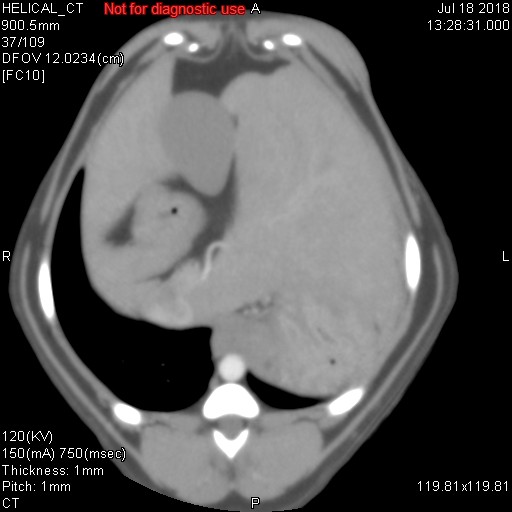

上記に載せました各写真ですが、CT検査で様々な条件で撮影した同一臓器(肝臓/胆嚢/胃/十二指腸/門脈/後大静脈/大動脈/肝動脈)です。CT検査では、そのまま撮影するプレーン、造影剤を使用する動脈相・門脈相・平行相がありますが、上記写真がどれかわかりますでしょうか??

シンプルに、一番上がプレーンです。臓器のシルエットくらいしかわかりません。その次が動脈相で、中央にピョろっとある肝動脈や背骨側にある太い血管(大動脈)が白くはっきりと写ります。また薄っすらと肝臓内にも多くの動脈がありますので、チラチラと動脈だけが見えてきます。3番目が門脈相といって肝臓の外にある門脈が白く際立ち、さらには肝臓内にある門脈(門脈枝)まで白くキレイに写ってきます。そして最後が平行相ですが、これは造影剤が通過して結構時間が経過した際の写真ですが、例えば具合が悪い臓器だと造影剤が抜けきるのが遅いため、時間が経過しているにもかかわらず造影剤がまだ残ってしまったりしますので、そのような際の評価に活かされます(あと悪性腫瘍など癌なども同じような見え方をします)。

造影剤を投与したあと20秒経過したときに撮影するのが動脈相、40秒が門脈相、120秒が平衡相といい、時間経過でCTスキャンを行って、様々な条件のもとで画像は分析されていきます。あと細かいですが、とある数字を設定して、その数字に達したらCTスキャンが開始されるなど、撮影方法にもいろいろあります。ただ単純にCTスキャンをしているだけではなく、造影剤を使用したり、投与時間を細かく設定したり、さらにいろいろな条件下で画像を比較して、最適かつ確実な画像診断を行っているのが、CT検査なのです。